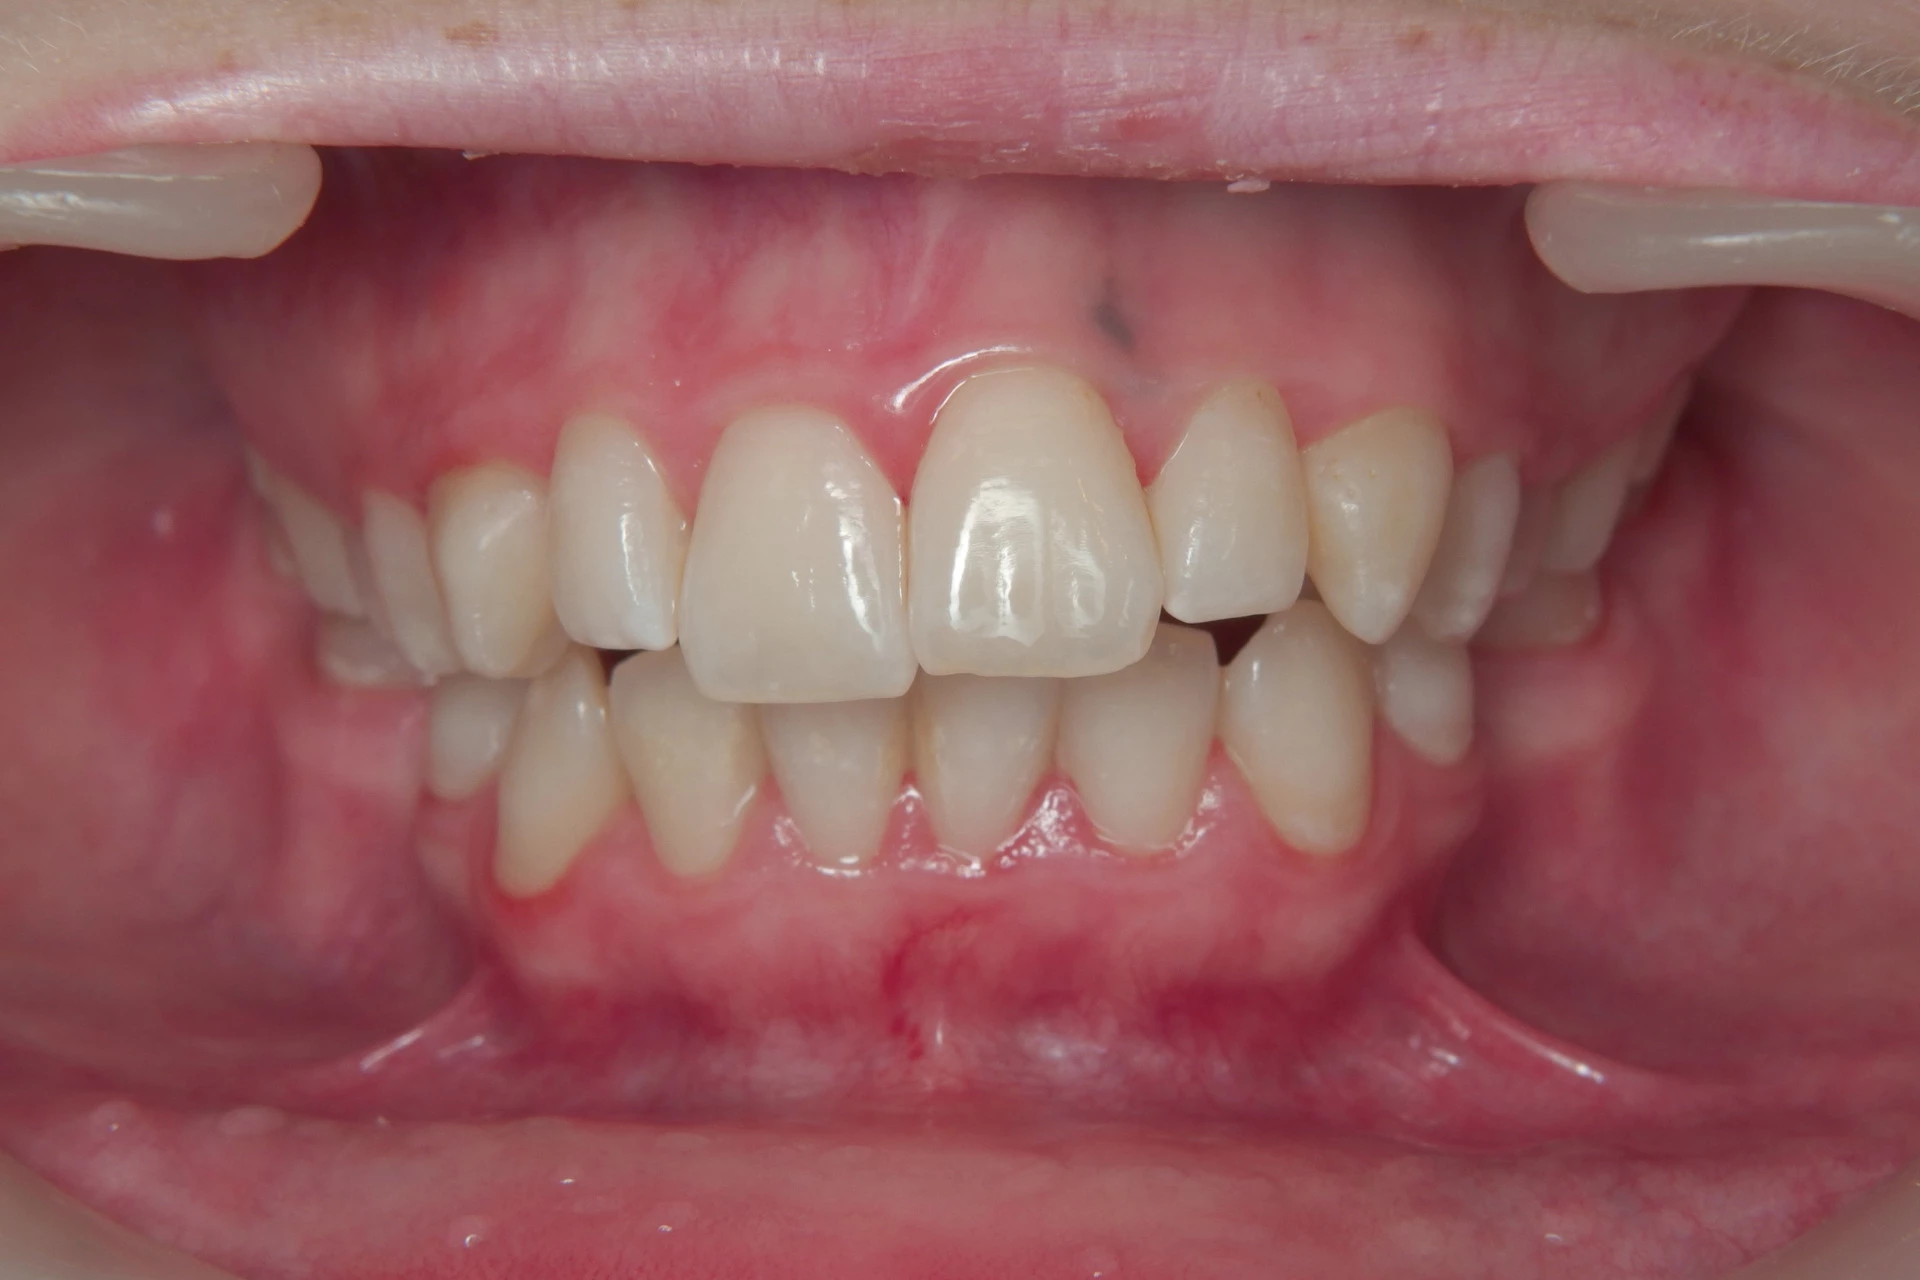

Vårt arbeid

Alle pasienter som vises har gitt skriftlig samtykke til at bildene kan brukes på klinikkens nettside.